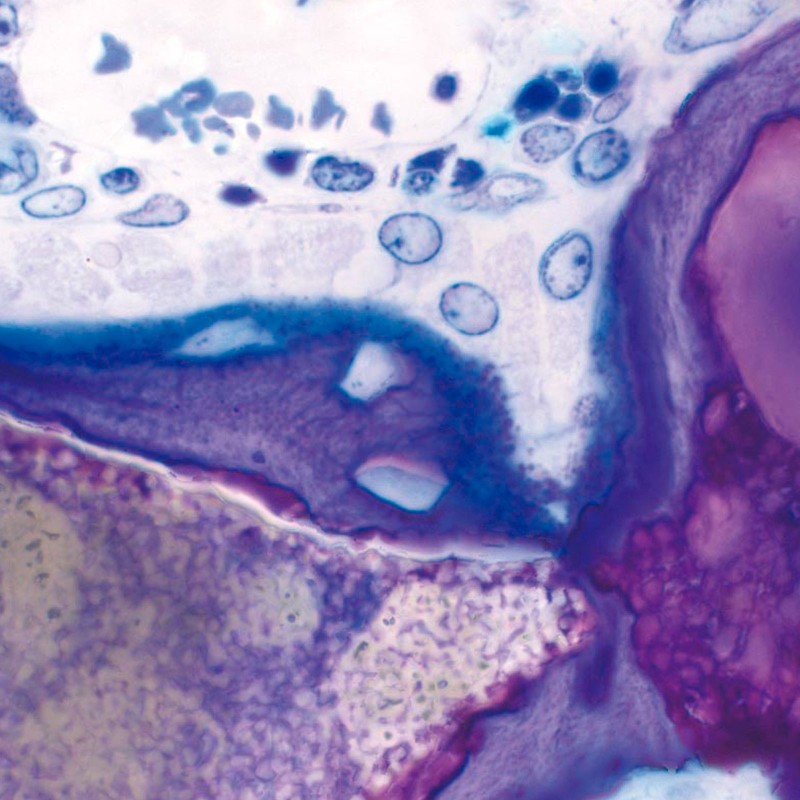

Porosidad interconectada ultra alta

La osteoconductividad de maxresorb ® se basa en una red de poros interconectados, una porosidad total muy alta de aprox. 80% así como su superficie muy rugosa 3, 4, 5 . La superficie nanoestructurada facilita la adsorción de sangre, proteínas y células madre y promueve la diferenciación celular y la integración ósea. maxresorb ® es, por lo tanto, un andamio ideal para la migración de células formadoras de hueso y la unión de moléculas de señalización, que pueden acelerar la integración y regeneración del tejido 6, 7 .

Aunque los resultados clínicos demuestran una regeneración algo más rápida de los defectos tratados con maxresorb ® , se recomienda seguir el mismo protocolo de tratamiento que para los materiales bovinos. En consecuencia, el reingreso después de procedimientos de aumento de cresta o elevación de seno con maxresorb ® debe realizarse 6 meses después de la operación. Este tiempo se puede acortar para la regeneración de defectos más pequeños o mezclándolo con hueso autólogo/alogénico.